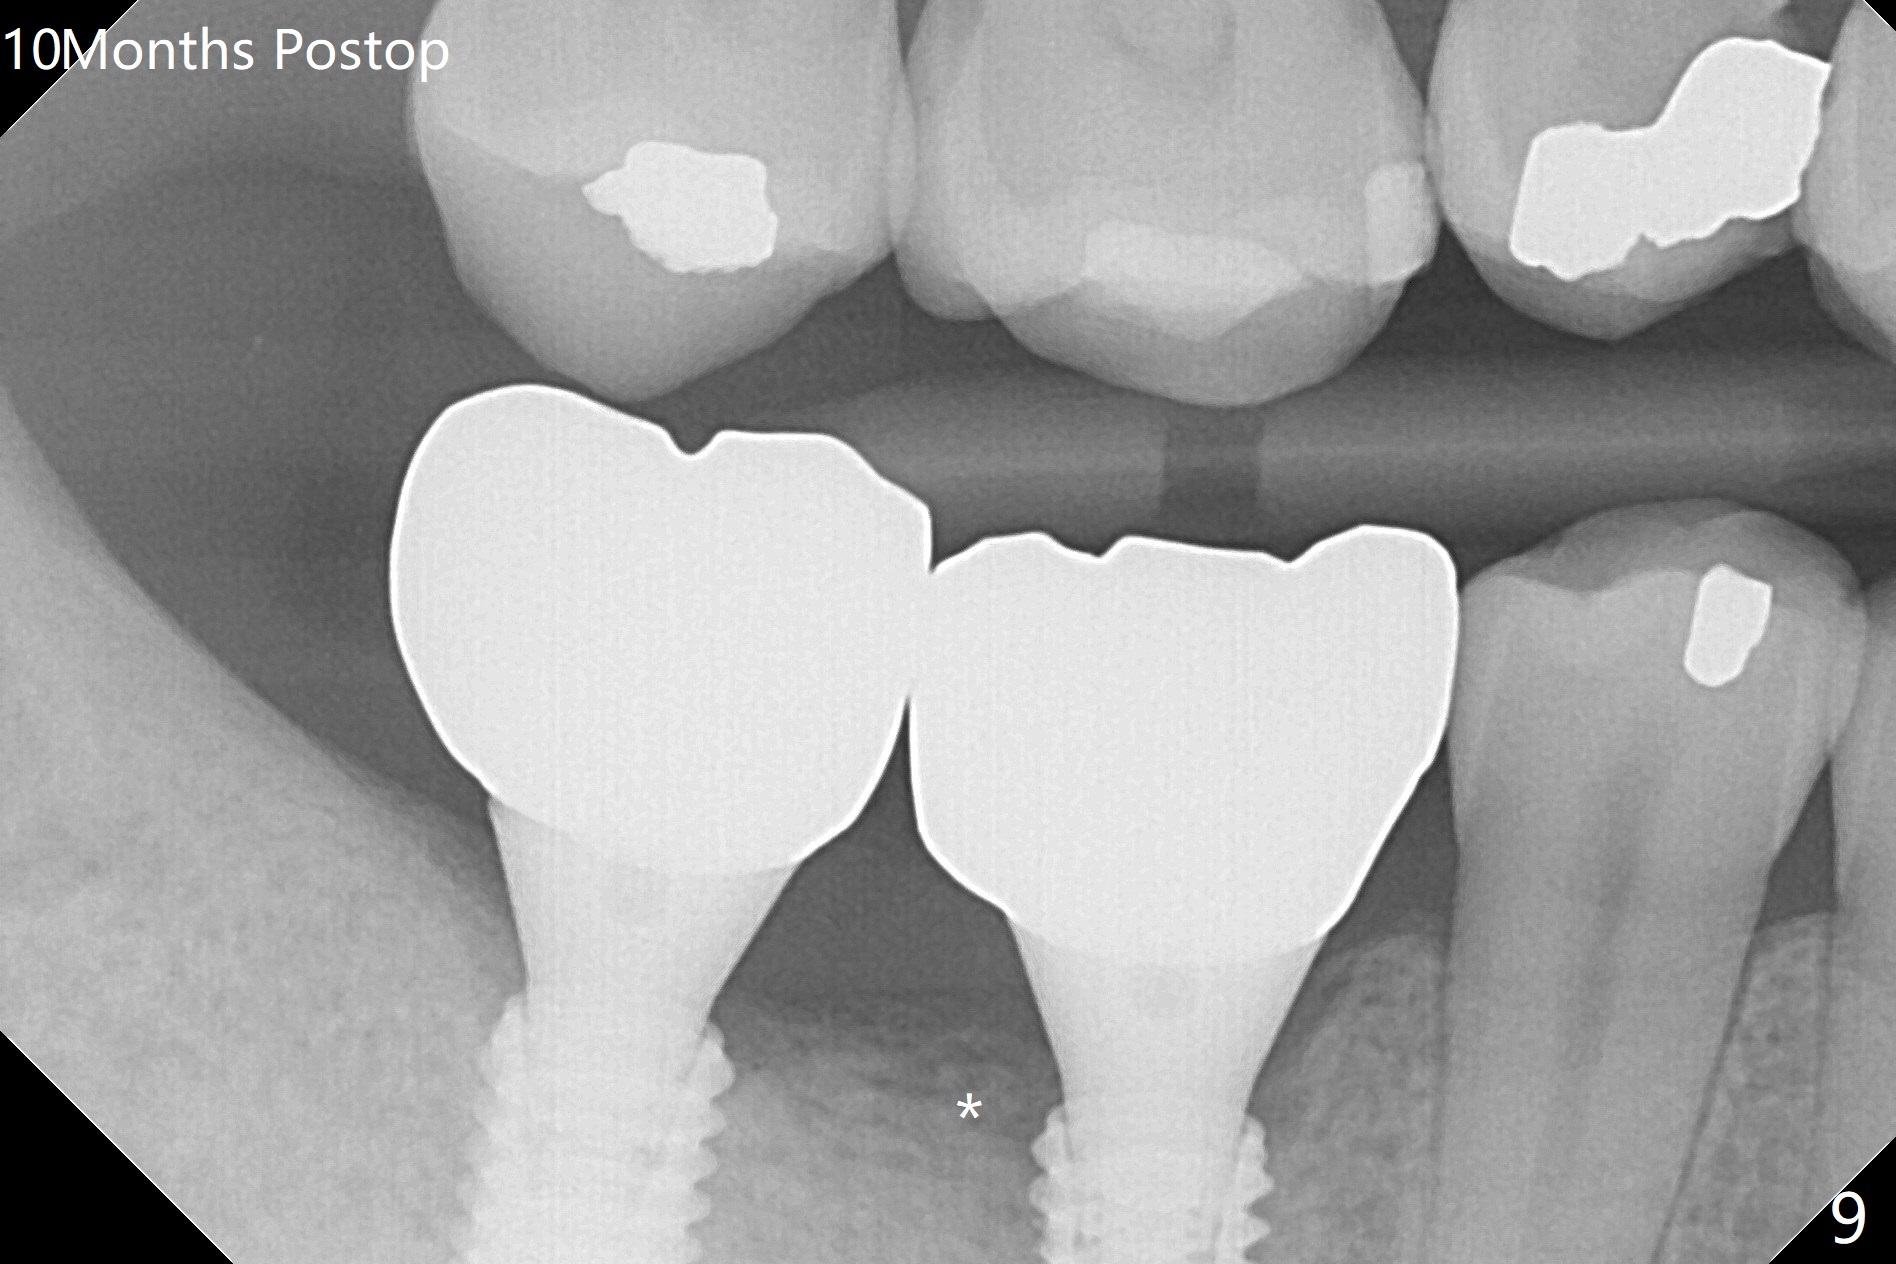

Infection is not so typical.  There is no recent postop X-ray, just 18-19 days postop.   Thanks for the reply.  We will keep watching.  The healing abutments, loose and associated with gingival inflammation, are removed 2.5 months postop (Fig.4).  There is crestal bone resorption, although the implants are stable.  The crestal bone resorption persists especially #30 distal 4 months postop (Fig.5 *).  When the implants are uncovered, there is mild bone loss distobuccal to #30 implant, consistent with early periimplantitis.  Bone graft is placed after debridement and healing abutment placement.  There appears no bone loss nearly 9 months postop (Fig.6).  The soft tissue looks healthy.  Cementation abutments (5.7x4(3) and 5.7x4.5(3) mm at #30,31, respectively) are placed for impression.  The distobuccal gingiva at #30 is hyerplastic 10 months postop (Fig.7 *, immediately before cementation), which is consistent with bone loss (Fig.8,9 * (periimplantitis)).  It is hoped that the infection will dissolve with improved oral hygiene (water pik) over the smooth final restoration.  In fact it is, i.e., the implants at #30 and 31 remain asymptomatic with the healthy gingiva 6 months post cementation (Fig.10,11).  There is mild crestal bone loss at #30 and 31 ten months post cementation (Fig.12).  Crown/implant ratio is the basis for screw loosening.  In fact the crown/abutment at #30 is loose 4 months later.  Incomplete seating of the abutment may be a culprit (Fig.12).  The gingival cuff is not healthy; a 6.8x7 mm healing abutment is placed with gingival blanching with Cetacaine and antibiotic ointment.  Next visit place a new smaller diameter abutment (4.5 or 5.2) with probably longer cuff (4 mm) or the existing abutment with no proximal contact crown, torque 25-30 Ncm and take BW with sensor 2 or PA with sensor 1.  In fact there is resistance to hand tighten a 4.5x4(4) mm healing abutment, which is due to contact with the mesial crest (Fig.13 *).  After use of 5.5 and 6.0 mm profile drills, the 6.8x7 mm healing abutment is reseated.  The latter appears to contact the mesial crest (Fig.14).  Later a 6x5 mm healing abutment is placed.  New crowns with new abutments are delivered 2 years 3 months postop (post Coronavirus lockdown).